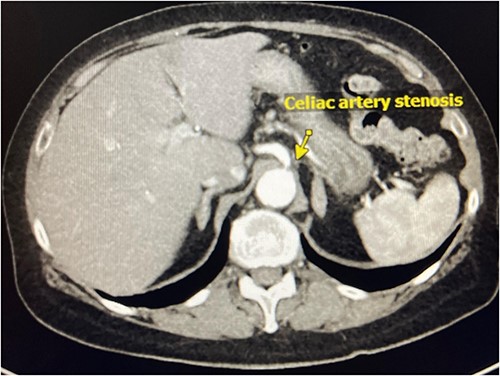

In the emergency department on presentation to our hospital, her vital signs were unremarkable and laboratory results were notable for a white blood cell count of 13 600 with left shift to 86% neutrophils. She underwent a computed tomography (CT) angiogram, which revealed an occluded SMA, severe celiac artery stenosis (nearly 90%), and a patent IMA (Fig. 1). A high-grade SBO was noted, possibly secondary to stricture, with transition point in the right lower quadrant (Fig. 2).

CT Angiography demonstrating celiac artery stenosis close to its origin.